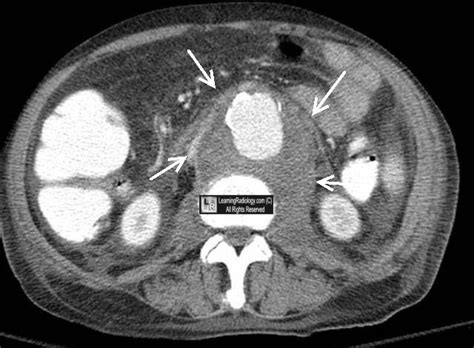

Draping Aorta Sign

Draping Aorta Sign. Web the “draped aorta” sign (↑) can indicate a recent rupture of the aorta. An aortic aneurysm is a weak spot in the wall of the body’s main artery, which is called the aorta.

Web the “draped aorta” sign (↑) can indicate a recent rupture of the aorta. The most common imaging features of mycotic aneurysm are periaortic soft tissue stranding and soft tissue mass. It is highly indicative of aortic wall deficiency. Symptoms include chest pain, fainting, and shortness of breath. However, of the four aa patients with the draped aorta sign in our sample, two showed no signs of rupture when they underwent surgery, and the other two had no index ct scan or reports of rupture or surgery in another service described in their medical. B axial enhanced ct of. Thank you for choosing to take an online vein screening with midwest aortic & vascular institute. Draped aorta sign can be seen in contained rupture of an abdominal aortic aneurysm. This sign is considered present when the posterior wall of an aortic aneurysm drapes or molds to the anterior surface of the vertebra. The draping aorta sign is considered present when the posterior wall of the aortic aneurysm drapes or moulds to.

A illustration depicts loss of normal aneurysm wall convexity. To evaluate the usefulness of a new computed tomographic (ct) sign of draped aorta in the diagnosis of a contained leak in an aortic aneurysm. B nect in axial view from the same patient also. Read about the causes, diagnosis, and treatment of this condition. In some patients, the first symptom is sudden death. An aortic aneurysm is a weak spot in the wall of the body’s main artery, which is called the aorta. Ct scans were retrospectively evaluated in 10 patients in whom an unidentifiable aortic wall and posterior aspect of the aorta that. Type a aortic dissection involves the ascending aorta and is surgically managed. Web the draped aorta sign on computed tomograms represents an early stage in the development of the pathological process, when the hemorrhage is contained by the fusion of the anterior renal fascia. Web hyperdense crescent sign and draped aorta sign are indicators of contained aortic leak or impending rupture. It is highly indicative of aortic wall deficiency.